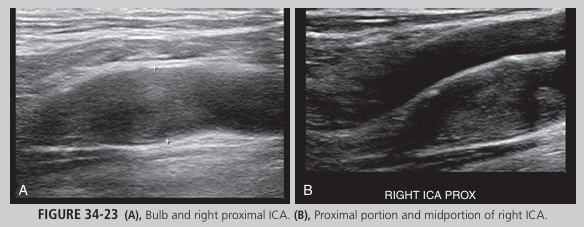

A 67-year-old man is taken to the hospital via ambulance. His symptoms include confusion, loss of memory, aphasia, and left sided hemiparesis. His history includes hypertension, hypercholes terolemia, and smoking. A carotid sonogram revealed echogenic material within the right internal carotid lumen. Images are pro vided in Figure 34-23. No flow was seen with spectral Doppler. What do these findings indicate?

right ICA occlusion